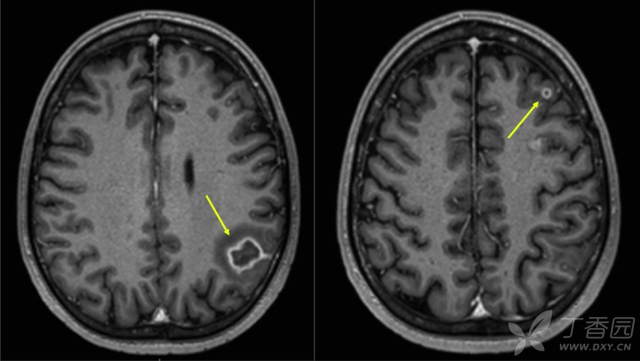

看图猜疾病 手脚都是 蔓越莓 答案公布在1楼

看图猜疾病 手脚都是 蔓越莓